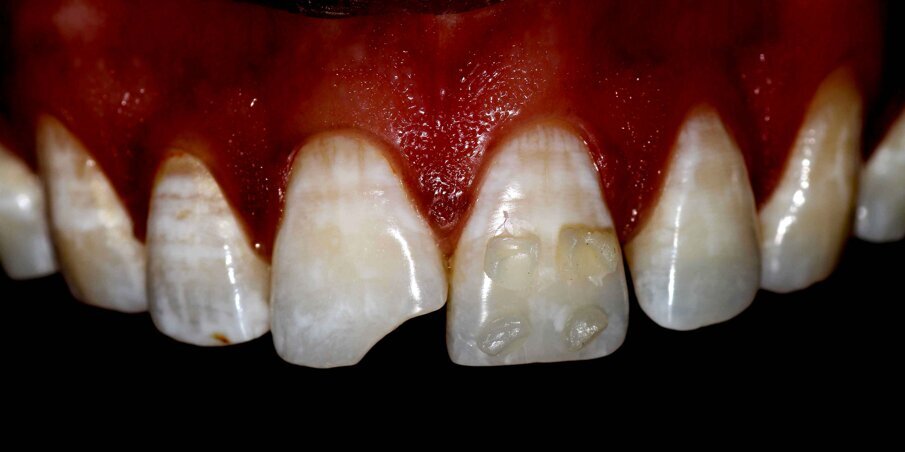

A 32-year-old man walks into our dental office with the chief complain of a broken front tooth. On examination, a Class IV fracture is seen involving the enamel and dentin of 11. The IOPA did not show any significant findings, and the tooth reacted positively to vitality testing.

It was decided to restore the tooth with Direct Composite Resin. Preoperative photographic records were taken. Small buttons of different shades (dentin, body and enamel shades of A1 and A2) of composite resin were placed on the adjacent teeth and photographs were taken with different settings to ascertain the correct value and chroma of the material to be used (button technique).

Fig 1: Pre op Smile

Fig 2: Pre op Intraoral